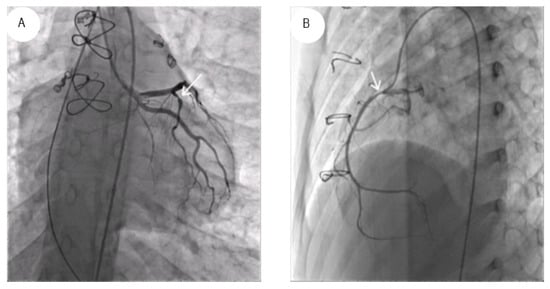

Coronary angiography is the accepted clinical standard for CAV diagnosis (Figure 6A,B). However, there are pitfalls in current ISHL grading for CAV based on coronary angiography. The categorical grading from CAV0 to CAV3 is based on discrete rather than continuous metrics [3]. This classification only detects more significant changes such as >70%, which is the cutoff for single primary vessel stenosis to be grouped as CAV2. A diagnostic test is better if it has higher accuracy, more reproducibility, is less invasive, less costly, has better significance for prognosis, and is useful to guide treatment. Intracoronary imaging with IVUS and OCT is better for diagnosing early CAV and satisfies many criteria for better imaging modalities.

Figure 6. Show severe epicardial CAV in the left (A) and right coronary artery (B).